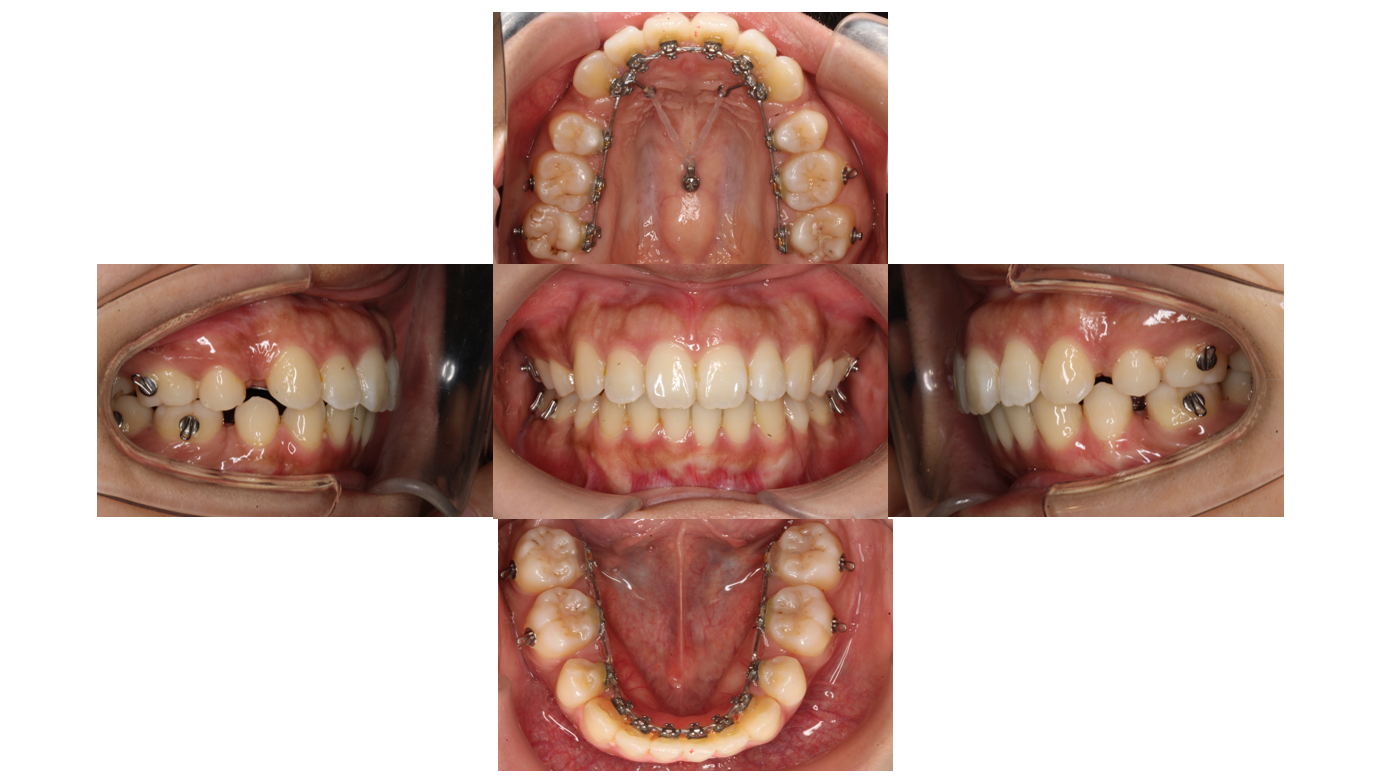

1年2か月経過

前回と同様に前歯を後ろに下げます